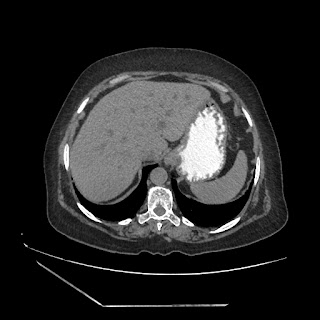

A 70 years old woman with Obstractive jaundice & palpable GB